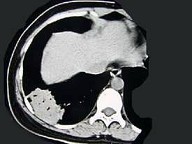

女,39岁,咳嗽伴轻微胸痛,CT检查如图,最可能的诊断是()

A.右下肺节段性不张

B.右下肺脓肿

C.右下肺周围型肺癌

D.右下肺炎性假瘤

E.右下肺肺泡细胞癌